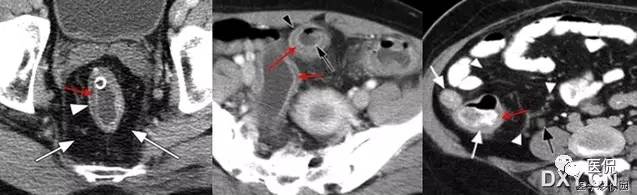

21 靶征(肠套叠)

是肠套叠最常见的特征性CT征像,为肠套叠长轴与CT扫描层面垂直时的表现,反映了套叠的各层肠壁、肠腔及肠系膜间的关系。典型排列为自外向内分别代表鞘部外层肠壁、鞘部肠腔内造影剂、鞘部内层肠壁、偏心性套入部肠系膜、套入部肠壁、套入部肠腔内造影剂。:

肠套叠是指一段肠管及与其相连的肠系膜(套入部)被套如其相连的一段长管内(鞘部),导致肠内容物通过阻碍。婴儿由于大肠与小肠管径之比例相差大。故小肠易陷入大肠而被套牢。少数肠套叠可能来自某些器质性病变如美凯尔憩室、肠息肉、异位胰腺小结、血管瘤、异物、复制肠管、淋巴增生、肿瘤、寄生虫等,其中以美凯尔憩室最多,过敏性紫斑也常会合并肠套叠,大于2岁的小孩发生肠套叠,一定要考虑到这些病变。大于5岁的病例中,则以淋巴瘤为最多;成人肠套叠小肠多见,常伴发良性病变;结肠型肠套叠则更多由恶性病变继发。良性病变有脂肪瘤、平滑肌瘤、血管瘤、神经纤维瘤、腺瘤样息肉、美克尔憩室、术后粘连机场动力性病变等;恶性病变有转移瘤、腺癌、类癌、淋巴瘤及平滑肌肉瘤等。由于肠套叠长轴与CT扫描层面的角度不同,表现各异。如扫描层面和迂曲的肠道相平行时,表现为彗星尾征或肾形征:即套叠近端肠系膜血管牵拉聚拢的征象。一般情况下,慧星尾征均与肾型肿块相伴出现。该肾形肿块为套鞘部游离缘与套入部近端肠管及肠系膜的CT斜切面图像,其中游离的套鞘呈弧形围绕套入部,形状若肾轮廓外形,而套入部近端肠管、肠系膜形状若肾蒂。此时,所谓慧星尾征的组成还应包括套入近端肠管。如果套叠的肠管与CT扫描垂直,则呈靶形征,即肿块影表现为圆形或类似环形。通常在肿块内可分辨出层样结构,推测可能是继发于套入部和鞘部间的液体或是肠壁水肿造成密度对比,类似同心圆形;当套入部肠壁显著水肿坏死或套入部肿瘤周围浸润累及肠系膜,肠系膜血管及脂肪、套叠时间较长,套入部系膜血管受挤压时,静脉血液回流障碍,套入部肠壁充血水肿、变硬,形成不完全性肠梗阻,套叠以上肠管蠕动增强,可引起代偿性肠管扩张肥厚,并可见肠系膜连同其血管纠集、扭曲,形成“漩涡征”。

成人肠套叠还有一些间接征象可帮助诊断,如肠壁不规则增厚或见密度不均匀的软组织块影,伴周围系膜及筋膜浸润、腹膜后淋巴结增大,则提示病因是恶性肿瘤。肿瘤所致肠壁水肿、坏死与部分炎症引起的套叠无法明确区分,肠壁及肠系膜血管有增厚伴肠壁内气体影的征象可提示血运障碍。如CT显示肠套叠直接征象、并伴随近段肠梗阻征象,则表示套入时间较长。如果套入部肠壁及鞘部组织发生水肿、变硬,形成不完全性肠梗阻,套叠以上肠管蠕动增强,可引起代偿性肠管扩张肥厚。

肠套叠形成的“靶征”

扫描层面和迂曲的肠道相平行时,表现为彗星尾征或肾形征:即套叠近端肠系膜血管牵拉聚拢的征象。